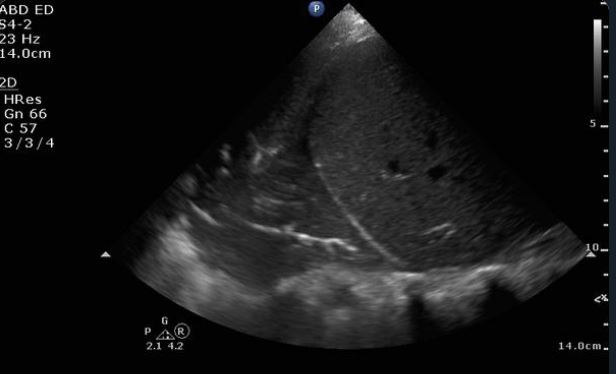

Feature image from: